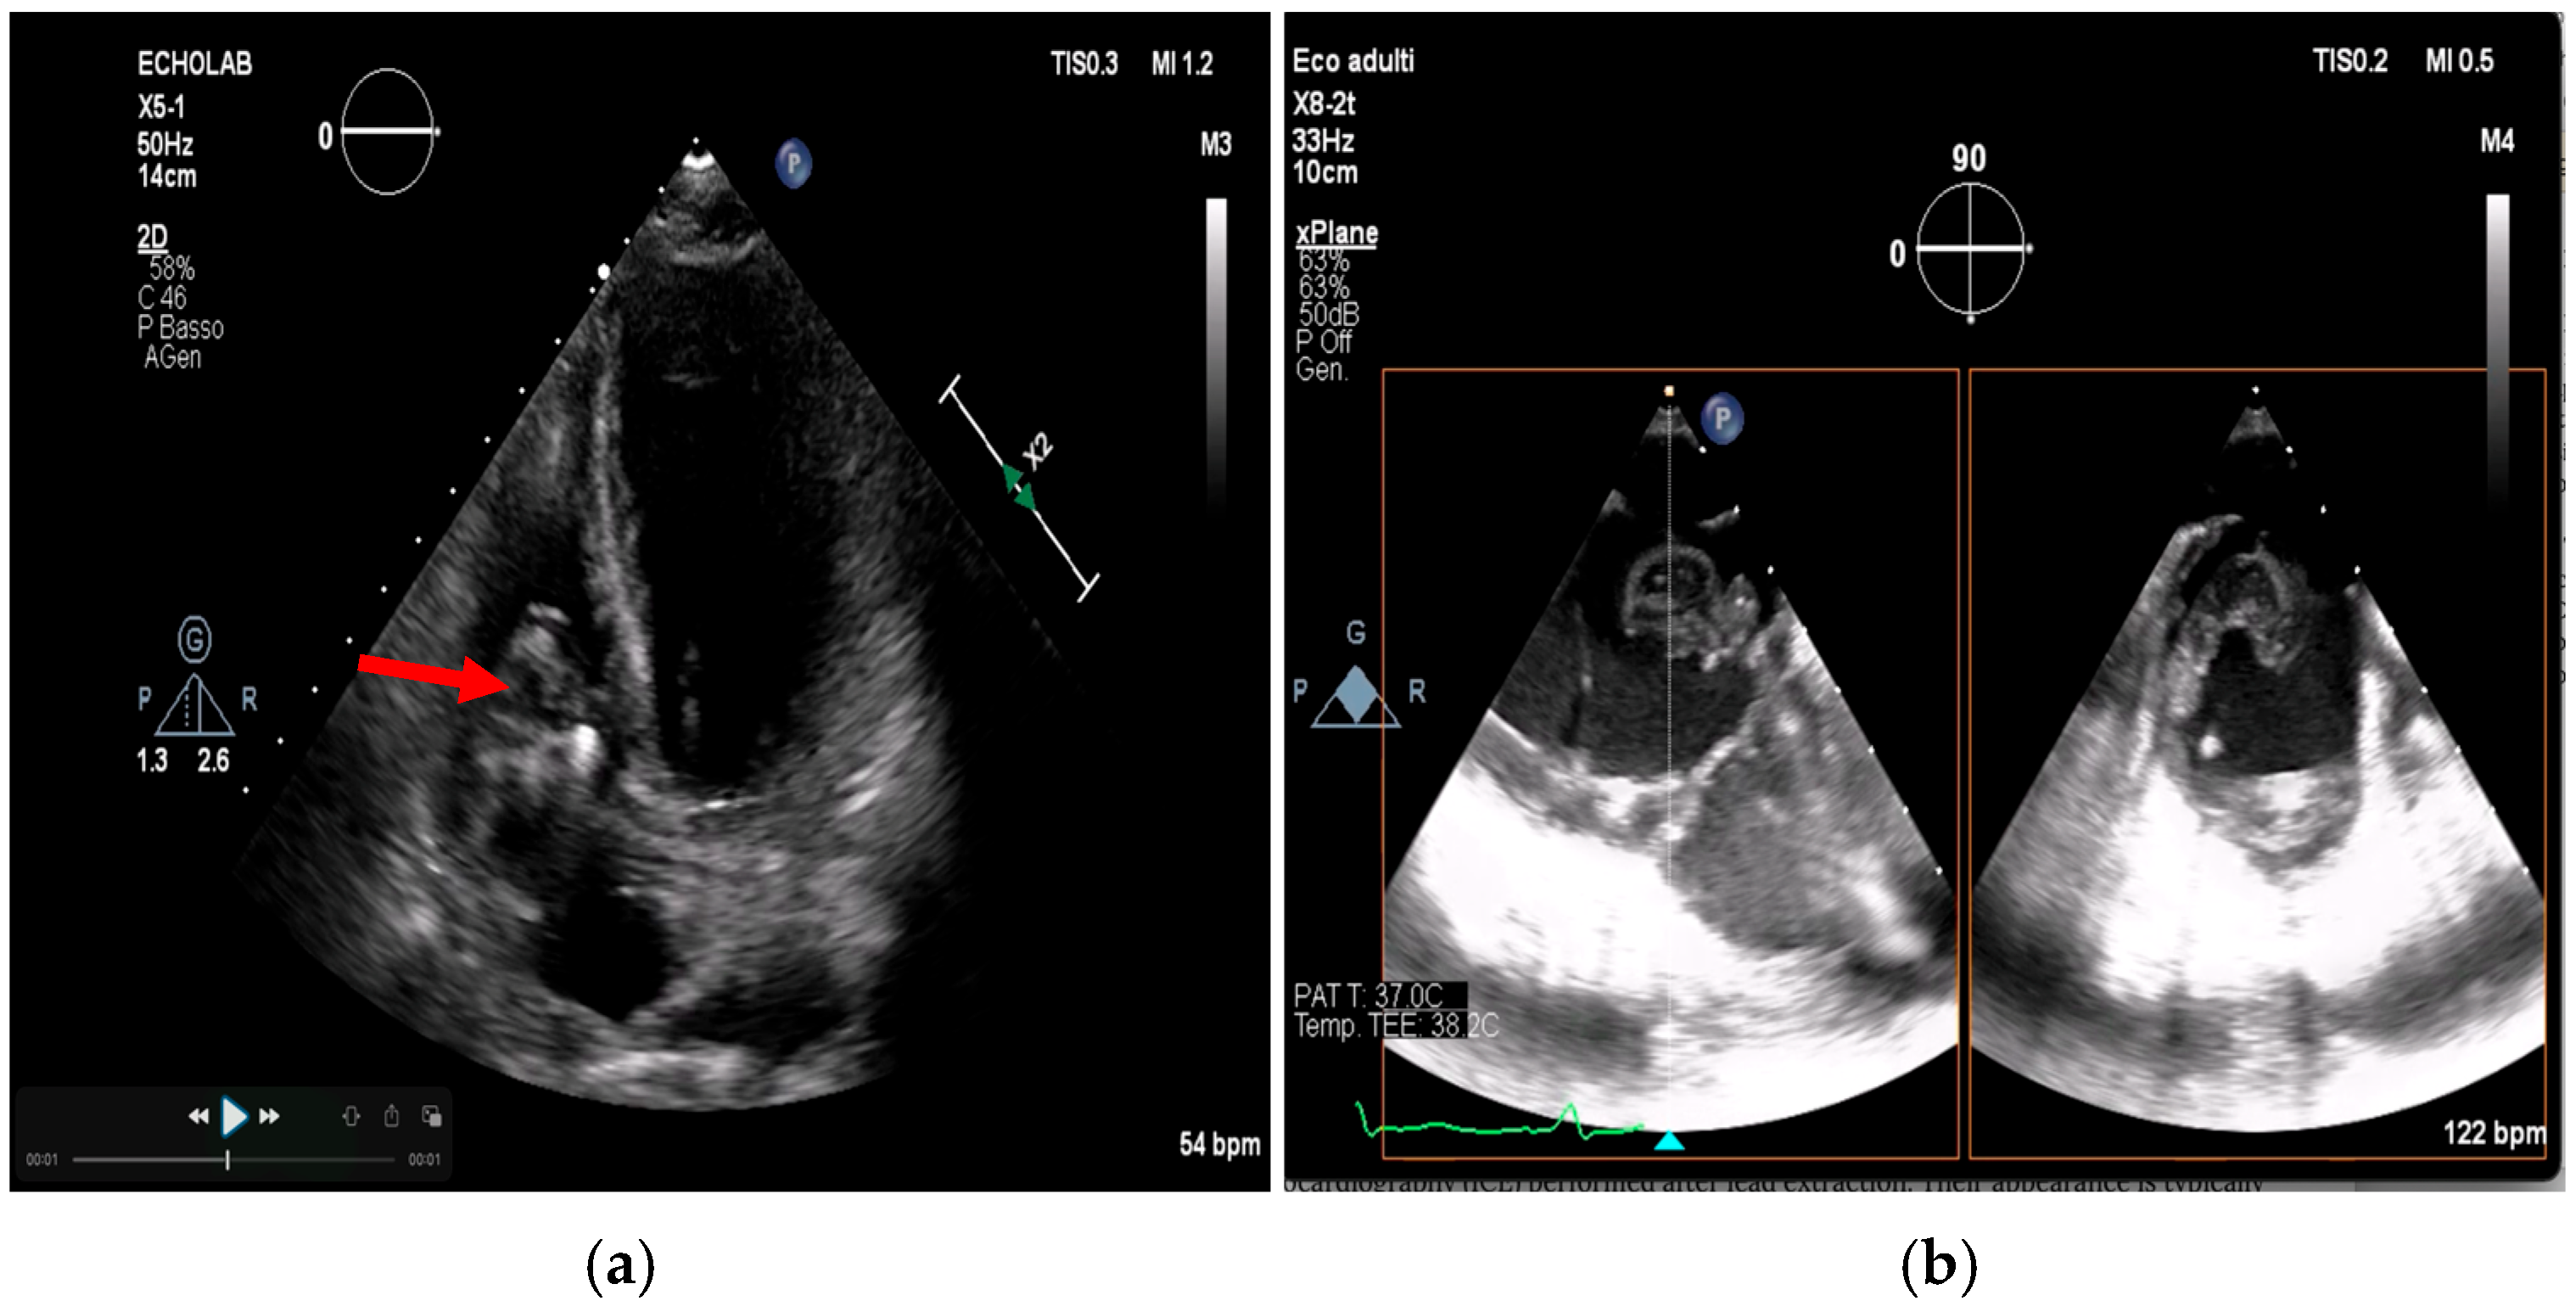

Advanced Imaging in Cardiac Implantable Devices

- Poterała, M.; Kutarski, A.; Brzozowski, W.; Tomaszewski, M.; Gromadziński, L.; Tomaszewski, A. Echocardiographic assessment of residuals after transvenous intracardiac lead extraction. Int. J. Cardiovasc. Imaging 2020, 36, 423–430. [Google Scholar] [CrossRef]

- Narducci, M.L.; Di Monaco, A.; Pelargonio, G.; Leoncini, E.; Boccia, S.; Mollo, R. Presence of ‘ghosts’ and mortality after transvenous lead extraction. Europace 2016, 19, 432–440. [Google Scholar] [CrossRef][Green Version]

- Le Dolley, Y.; Thuny, F.; Mancini, J.; Casalta, J.-P.; Riberi, A.; Gouriet, F. Diagnosis of Cardiac Device–Related Infective Endocarditis After Device Removal. JACC Cardiovasc. Imaging 2010, 3, 673–681. [Google Scholar] [CrossRef]

- Li, Y.; Jiang, L.; Wang, L.; Han, Q.; Yin, X.; Feng, Y. Ghost in the right atrium: A case report on successful identification of residual fibrous tissue. Heliyon 2023, 9, e21982. [Google Scholar] [CrossRef] [PubMed]